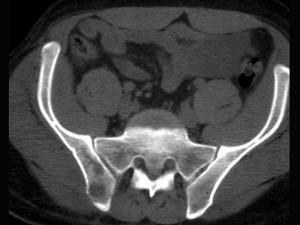

问题 女,38岁,腰背和右侧骶髂关节痛,请结合图像,选出最可能的诊断 ( )

选项 A、骨巨细胞瘤 B、骨髓瘤 C、类风湿关节炎 D、右髂骨结核 E、化脓性关节炎

答案 D